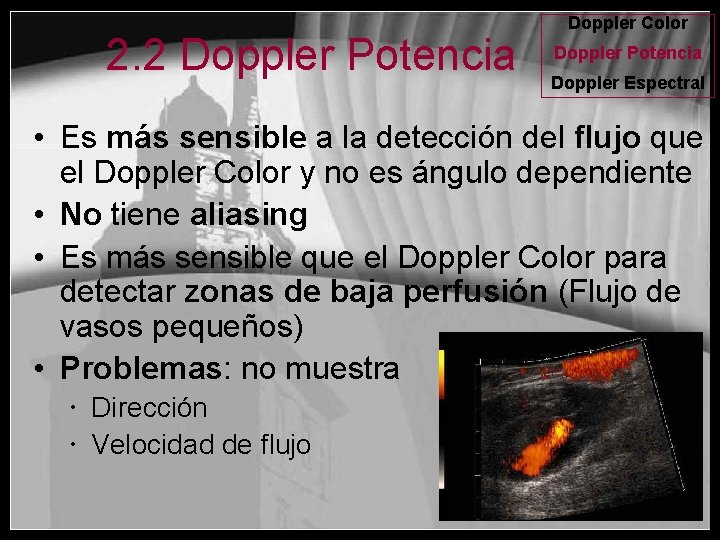

2. 2 Doppler Potencia Doppler Color Doppler Potencia Doppler Espectral • Es más sensible a la detección del flujo que el Doppler Color y no es ángulo dependiente • No tiene aliasing • Es más sensible que el Doppler Color para detectar zonas de baja perfusión (Flujo de vasos pequeños) • Problemas: no muestra Dirección Velocidad de flujo